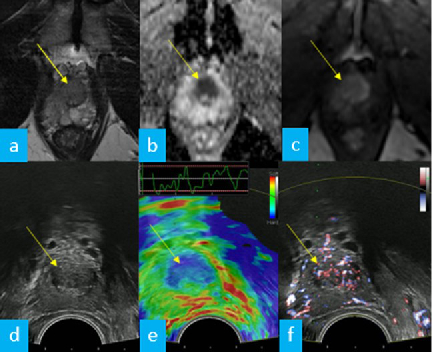

Imaging and Targeted Biopsy of the Genitourinary (GU) Tract

Friedrich Aigner

- Multiparametric ultrasound of the scrotum

- Multiparametric ultrasound of the prostate

- Multiparametric MRI of the prostate

- Fusion imaging of the GU-tract

- Fusion targeted biopsy of the prostate

The simultaneous application of structural and functional imaging techniques is described as multiparametric (MP) (Fig. 9). Studies have shown that the MP approach results in greater diagnostic accuracy (Fig. 10).

The use of fusion imaging in uroradiology improves ultrasound lesion-detection rates, shows more reliable size controls at different time points, is an alternative to in-bore biopsies (Fig. 11) and can be used for focal therapy.